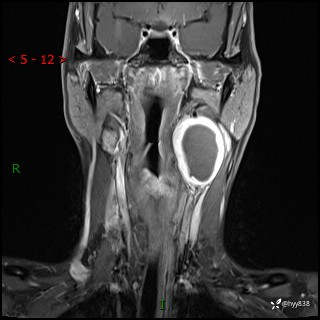

年轻小伙,发现左侧颈部肿物3年余,逐渐增大---结果公布~

现病史:患者约3年前因感冒发现左侧颈部长一肿物,约半个鸡蛋大小,无明显疼痛及其他不适,一直未行特殊处理。3个月前发现左侧颈部肿物变大,随后至当地市第二人民医院耳鼻喉科行左侧颈部彩超示:左侧颈部囊实混合性包块;喉部MPR示:左侧胸锁乳突肌内前方占位,累及左侧喉旁间隙,建议增强扫描。建议手术治疗。患者考虑。随后至我院肿瘤科就诊,行细胞学穿刺示:考虑血管源性肿瘤可能,建议进一步检查。建议至我院口腔科就诊,行颌面部MRI示:左侧颌下腺后方团状异常信号灶,建议增强。建议手术治疗。为求进一步治疗,门诊以“左侧颈部肿物”收入院。 起病以来,患者神志清、精神良好,饮食睡眠良好,大小便正常,体重未见明显变化。

颈部MRI平扫+增强